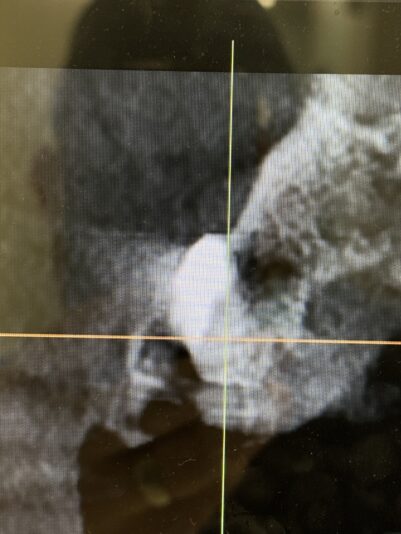

• This case I posted last year when I was planning. Here it is at 5 months, I am concerned about the buccal plate width at the mid/apical third. Clearly should have put this more lingual. Long term predictability?

1

• View 1 reply

• Immediate #8, I did graft the buccal gap, but boy did that resorb :/